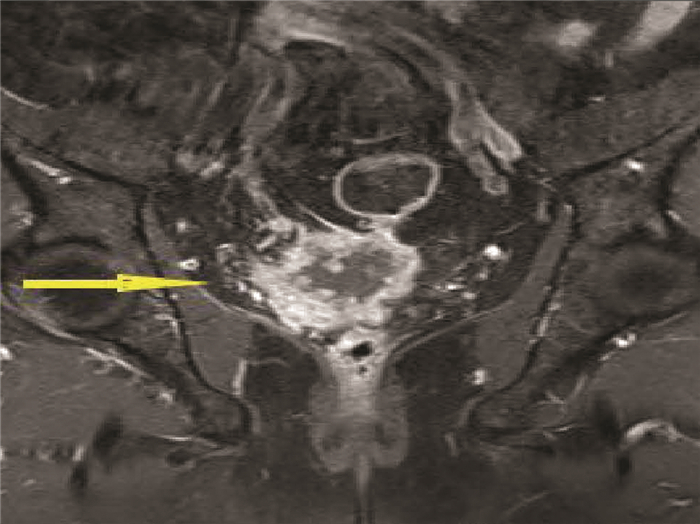

Primary liver cancer with prostate metastasis: A case report